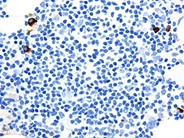

A CD20 (L26)immunostain for the presence of B-cells shows only a rare positive cell to be present.